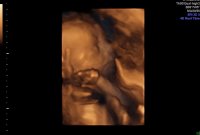

Har noen tenkt på om de skal ta enda en ultralyd med 3D av fjes?

Er det verdt det, noen erfaringer? Kan man virkelig se fjeset?

det frister, men er jo dyrt og hva hvis bildene uansett ikke blir noe tydelige? Ligner det i det hele tatt på «sluttresultatet»?

og ikke minst, når tar man det??

nå er de litt forskjellige.. guttungen ligner på faren mens jentungen er prikklik meg som liten!